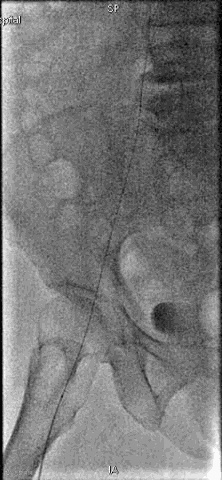

手术过程

抽吸结果